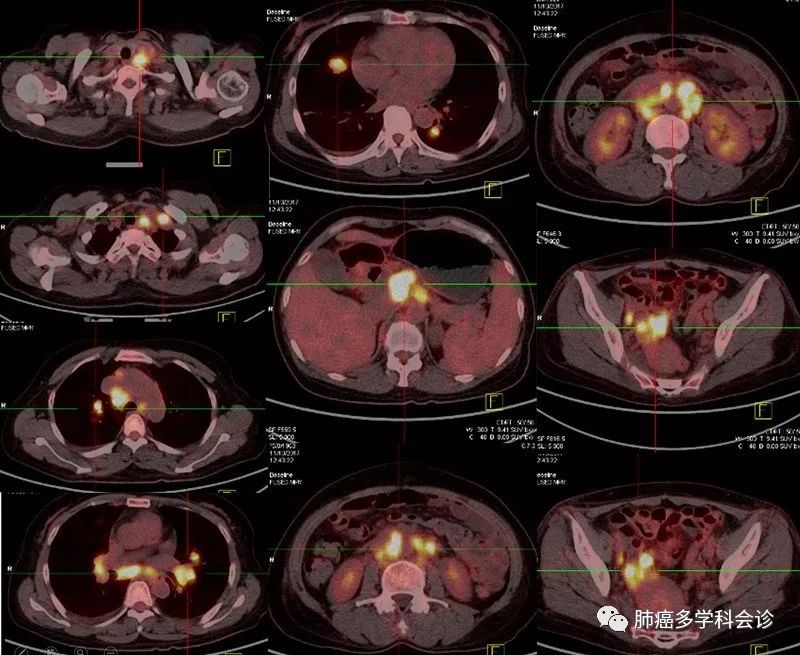

于2017年11月做PET-CT示:右侧附件区软组织肿块代谢活跃,考虑恶性病变;双肺多发结节影部分代谢活跃,胰腺内结节样代谢活跃灶,双侧颈部、纵隔、双肺门、膈上、腹腔、腹膜后及双侧髂血管旁多发肿大淋巴结代谢活跃,考虑转移;右侧胸腔积液,盆腔积液。